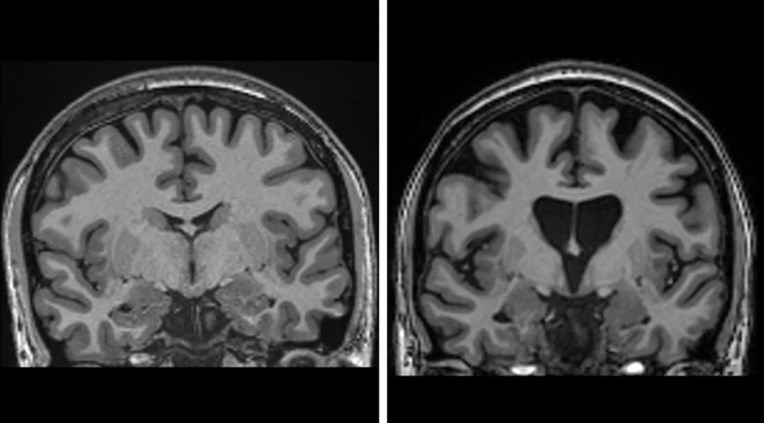

U REVOLUCIONARNOM kliničkom ispitivanju, liječnici su po prvi put uspjeli uspješno liječiti Huntingtonovu bolest, razornu nasljednu bolest koja postupno uništava moždane stanice. Nova genska terapija usporila je napredovanje bolesti za čak 75 posto kod pacijenata tri godine nakon tretmana, piše The Guardian.

Ova bolest, uzrokovana defektom na jednom genu, dovodi do demencije, paralize i na kraju smrti. Osobe čiji roditelj ima Huntingtonovu bolest imaju 50 posto šanse da je naslijede, a do sada nije postojao lijek koji bi zaustavio njezino napredovanje.

Rezultate ispitivanja, koje je obuhvatilo 29 pacijenata u Ujedinjenom Kraljevstvu i SAD-u, objavila je tvrtka uniQure. Tri godine nakon liječenja, pacijenti koji su primili visoku dozu lijeka pokazali su prosječno 75 posto sporije napredovanje bolesti, mjereno testovima motoričkih funkcija, kognicije i sposobnosti obavljanja svakodnevnih aktivnosti. Također, nalazi su pokazali značajno niže razine neurofilamenata, markera stanične smrti, što ukazuje na zaštitu neurona.